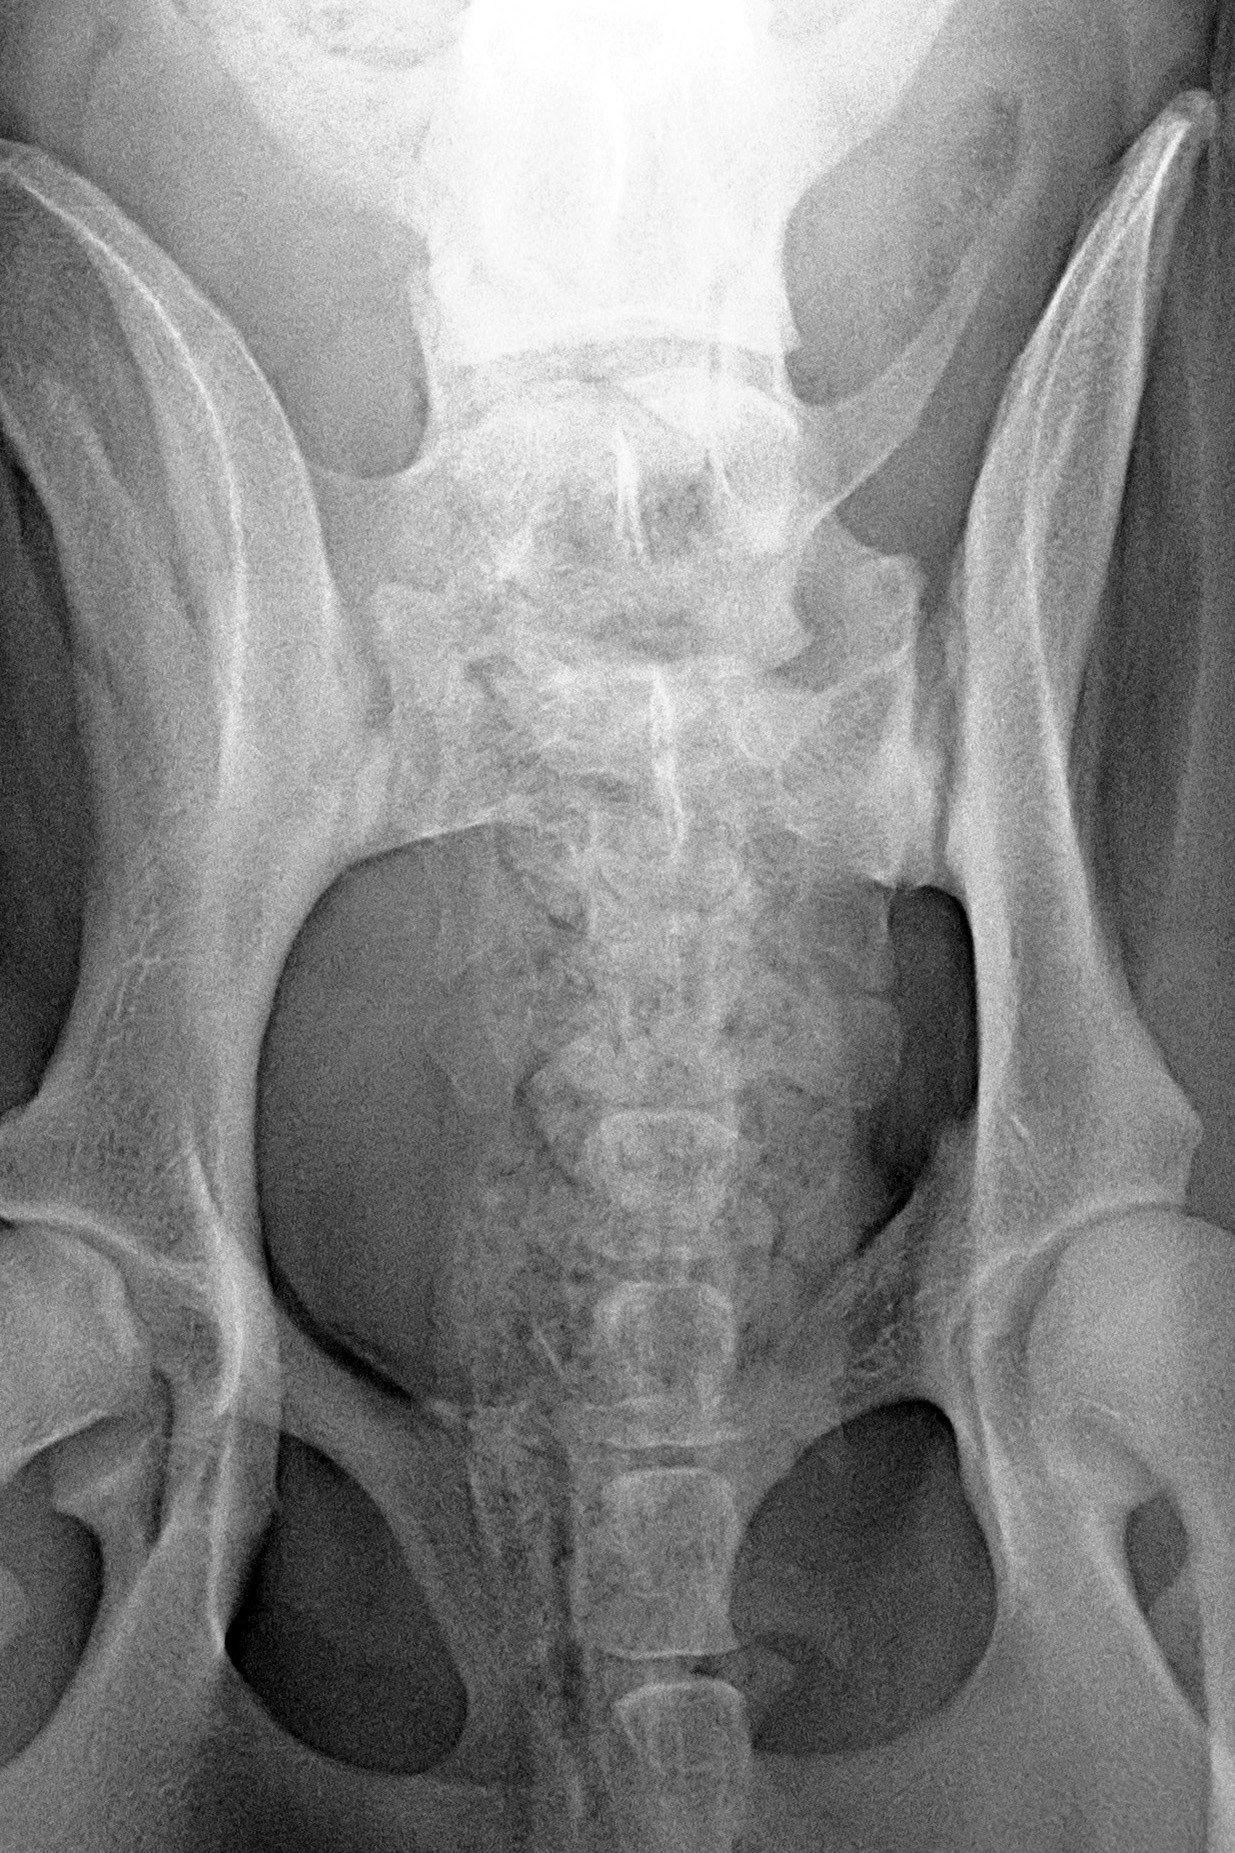

(3) 7 měsíců VD 1

(3) typ 3 po korekci polohy pánve

(4) 7 měsíců VD 2

(4) typ 3 po korekci polohy pánve 2